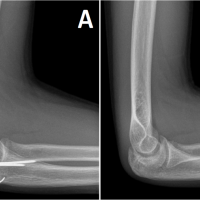

A 26-year-old man with Type III OI and a history of correction osteotomy and intramedullary Kirschner wire fixation in his right humerus at the age of 8 years felt gradually increasing pain in his humerus. His left upper limb and both lower limbs were not functional, and he lived in an electric wheelchair. He was unable to manually operate the wheelchair and instead moved it with a switch using his right hand. His right upper limb was his only functional extremity. He had developed humeral shaft non-union due to a broken Kirschner wire used in the previous operation. He was referred to our hospital and underwent internal fixation using an intramedullary elastic nail with an autogenous iliac bone graft. However, 2 years after the operation, bony union was not achieved and elastic nail breakage had occurred, and he complained of pain and limitation of activity (Fig. 1). He underwent a re-operation for his humeral non-union using a locking plate to achieve rigid fixation. Since his humeral shaft was extremely narrow with severe deformity, we used a locking plate for the mandibular bone, which was contoured to fit the medial side of the humeral shaft (Fig. 2). Bony union was achieved, and he became free from pain and returned to his pre-injury activity with no symptoms. No implant failure or refracture of his humeral shaft had occurred 4 years later, but a new fracture line was found in radiographs of the distal part of the non-union (Fig. 3). We used a cast to fix the new fracture for 9 weeks and then a splint for 4 weeks.He recovered well, and at the time of this writing, he was maintaining normal function of the right upper limb and was able to perform activities of daily life without problems.